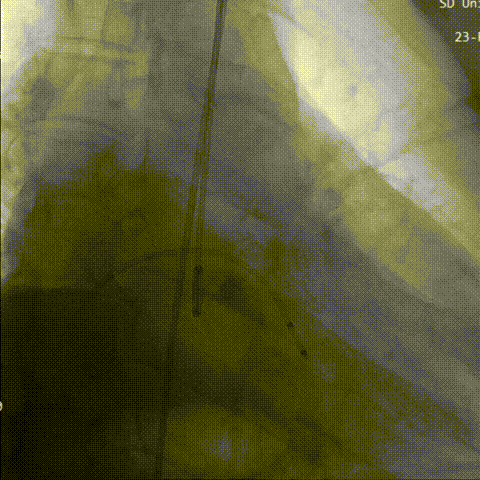

最后三分之一瓣膜稳定脱钩,造影显示,无明显瓣周漏及反流,瓣膜形态佳,工作稳定。

瓣膜完全释放

猪尾造影评估

术后即刻评估